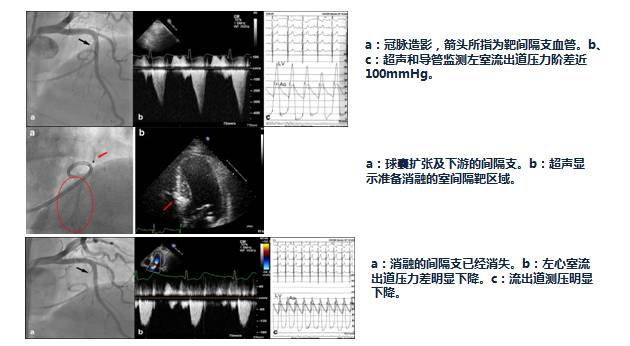

入院第5天行选择性冠脉造影+室间隔化学消融+ICD植入

◆左、右冠状动脉未见明显狭窄,前降支第一、第二间隔支消失,第三间隔支存在。

◆测压:左心室 235/12mmHg;左室流出道 162/27mmHg;主动脉108/57mmHg。

◆先植入单腔ICD,再消融第三间隔支。